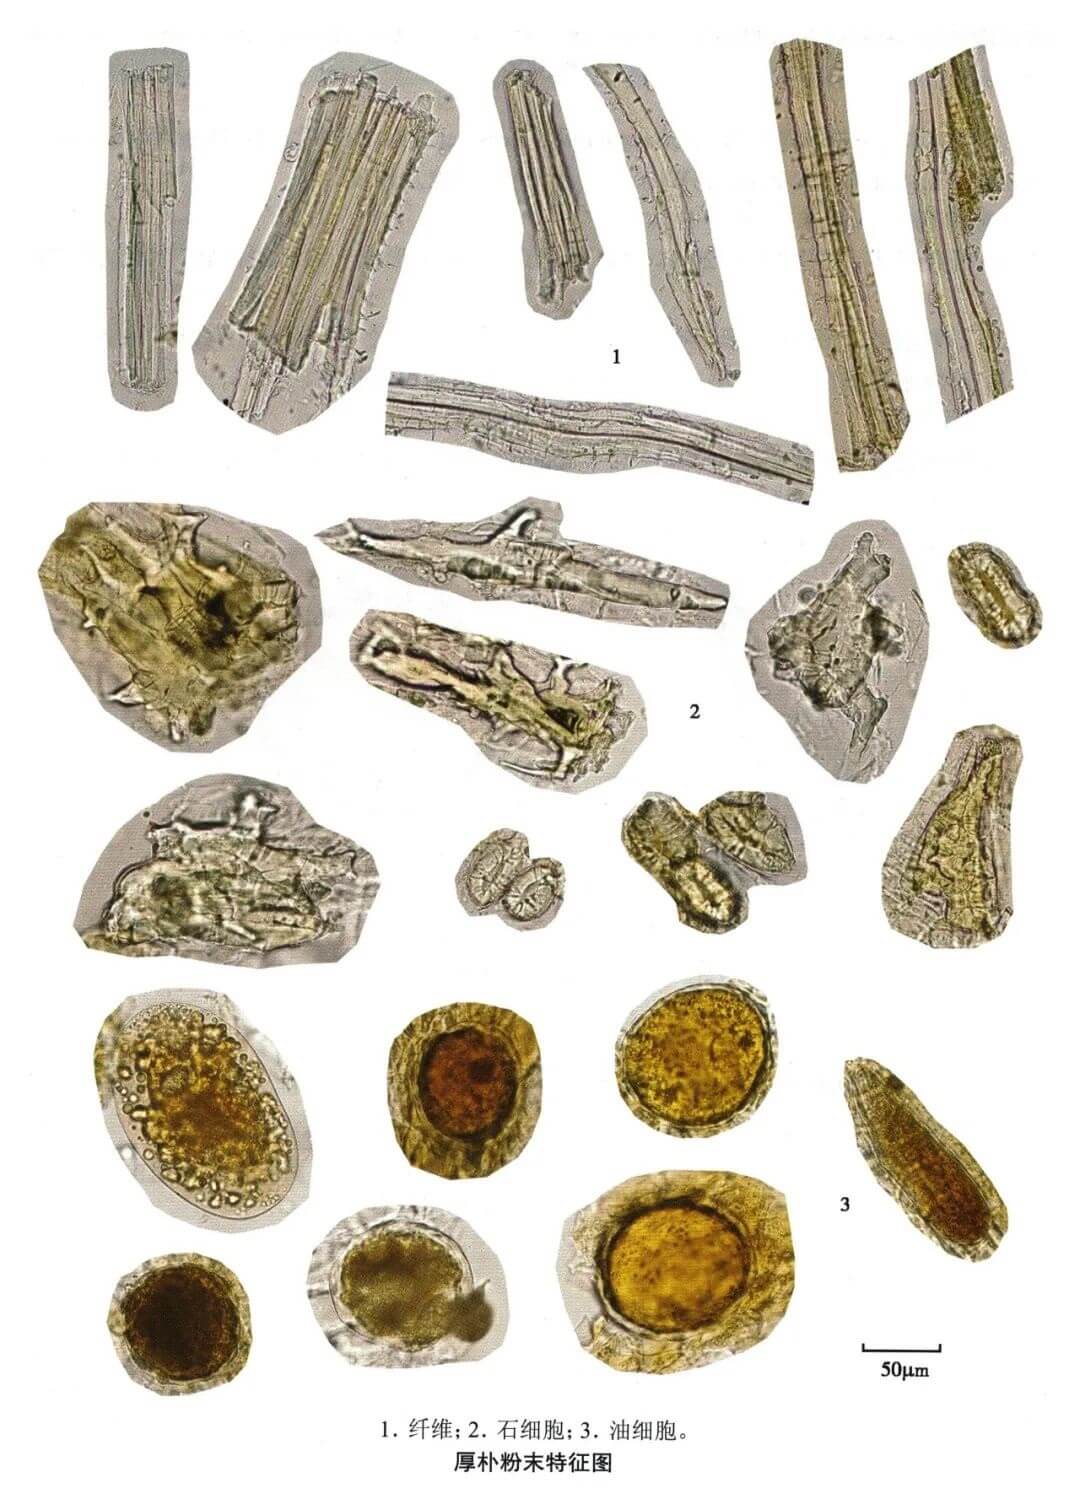

厚朴

| 厚朴 |

|---|

| 【参考标准】 《中国药典》2020年版一部 |

| 【显微鉴别】 粉末棕色。纤维甚多,直径15~32μm,壁甚厚,有的呈波浪形或一边呈锯齿状,木化,孔沟不明显。石细胞类方形、椭圆形、卵圆形或不规则分枝状,直径11~65μm,有时可见层纹。油细胞椭圆形或类圆形,直径50~85μm,含黄棕色油状物。 |

| 【显微重点】 油细胞需要用水合氯醛不加热才容易找到;石细胞的形态。 |

| 【图谱来源】 《中药成方制剂显微图典》 |